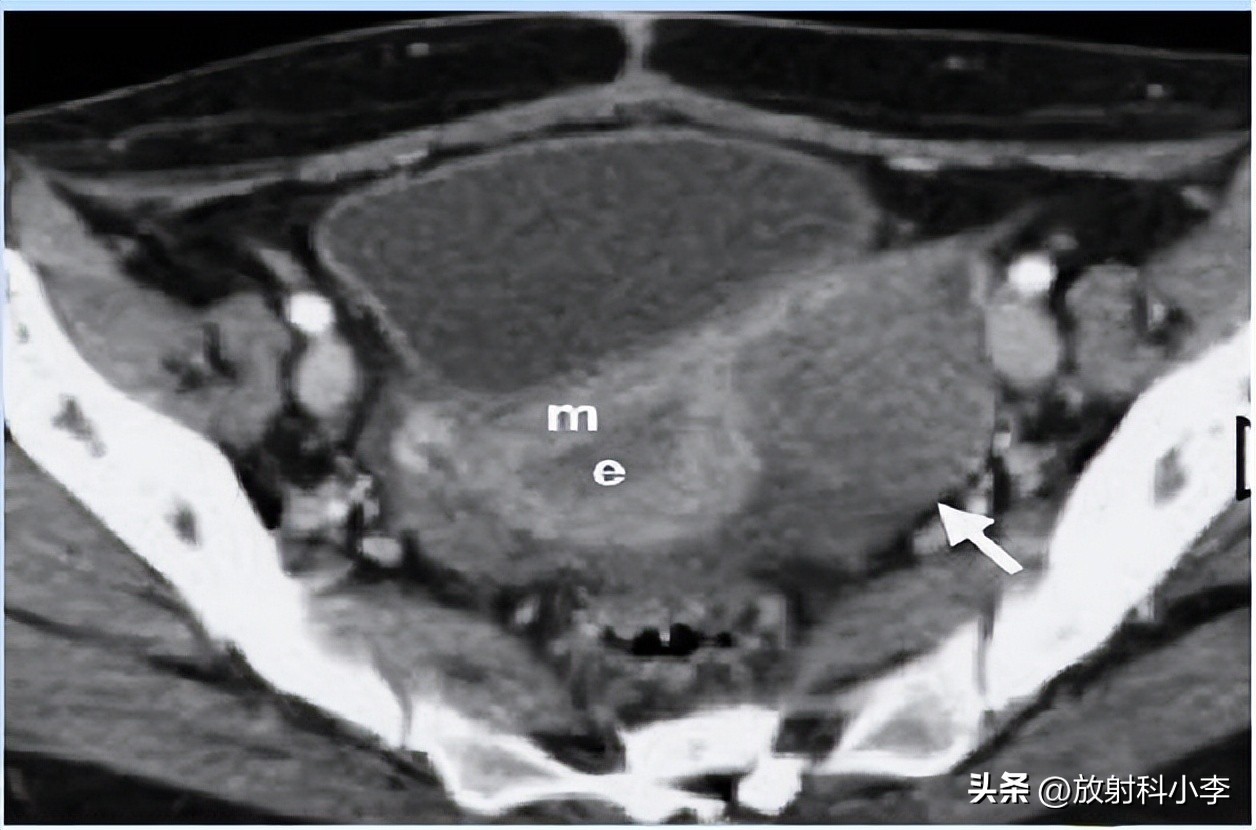

case 2. F,84Y

3年前的CT平扫示:左侧附件区肿块,主要呈实性,平扫密度较高,伴出血;3年后CT示:左侧附件区肿块较3年前明显增大,呈囊实性,实性成分为主,增强强化轻或无,瘤周见条带影/团块影与子宫相连。